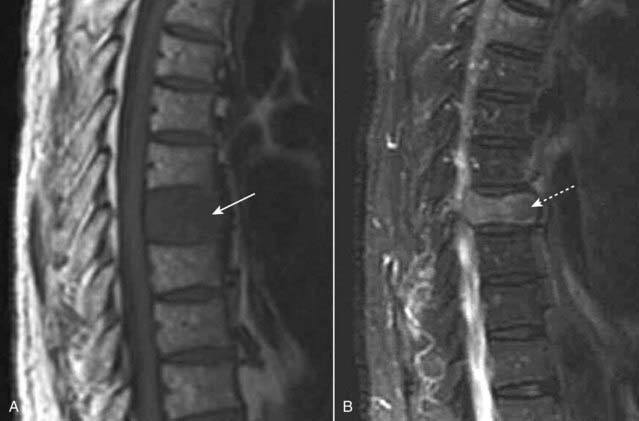

imageWith neoplastic infiltration of the bone marrow, there is a decrease in the normally high signal of the vertebrae on T1-weighted images and there is usually a high signal on T2-weighted images (Fig. 24-16).

Figure 24-16 Metastases to the spine, MRI.

A, T1-weighted sagittal MRI of the thoracic spine demonstrates marrow replacement in the T8 vertebral body (solid white arrow). The signal is decreased compared to the normal bodies above and below it. B, T2-weighted sagittal MRI shows abnormally high signal in the compressed vertebral body (dotted white arrow). The entire vertebral body is involved. The patient had primary breast carcinoma.